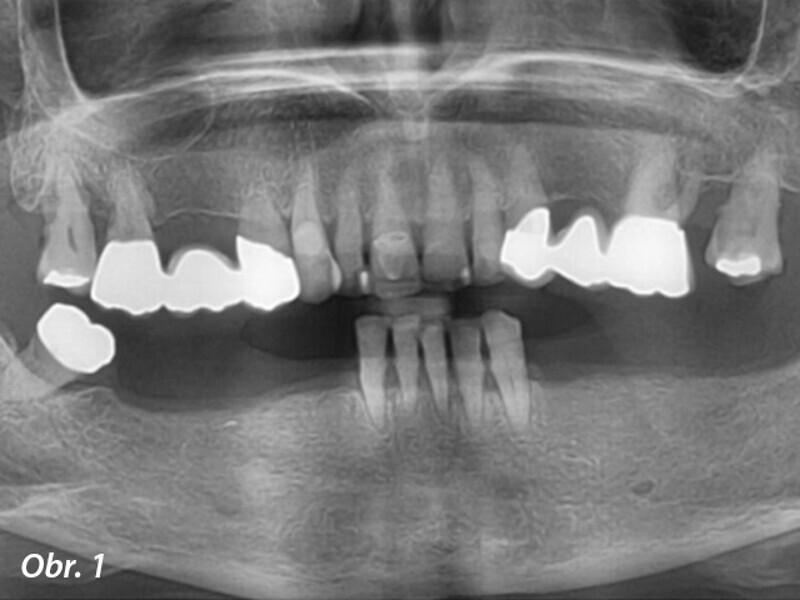

Počítačem asistované, šablonou se řídící okamžité zavedení a zatížení implantátu v dolní čelisti